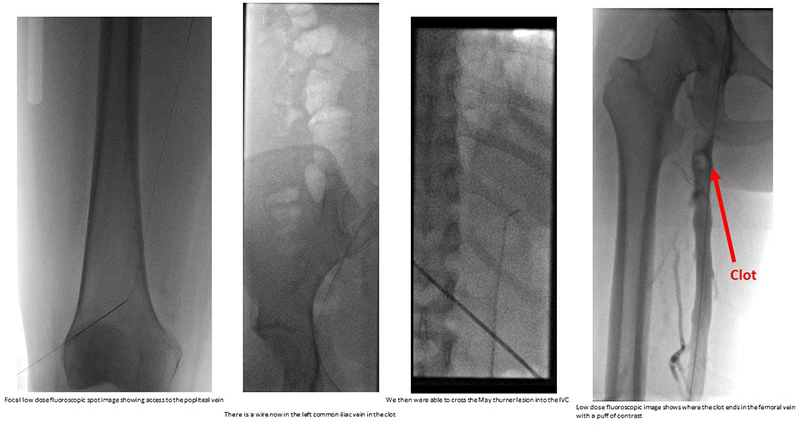

Ultimately, we decided the appropriate course of treatment would be adjunctive endovascular intervention, called mechanical suction thrombectomy. The clot she had was substantial. We were especially worried that if this clot were to be dislodged and sent to the heart, it would risk cardiopulmonary compromise and cause the heart to stop beating. In the past, these procedures required tPA (tissue plasminogen activator), a drug which can dissolve blood clots, but can cause severe uncorrectable bleeding. Recent advances in technology, offered at NewYork-Presbyterian, have allowed for a much safer way to debulk this clot and can be performed safely and minimally invasively. We were concerned about the use of radiation that this procedure requires, especially in this pregnant patient in her first trimester, but we were able to use additional tools to minimize that risk.

Remnants of the blood clot after the mechanical thrombectomy

We performed a low-dose diagnostic venography and intravascular ultrasound which demonstrated an occlusive thrombus extending throughout the left common iliac vein, left external iliac vein, and left common femoral vein. We accessed the popliteal vein in the back of her knee and used a large bore catheter to debulk the clot from the knee (peripheral) to the lower abdomen (central). We successfully evacuated the clot with minimal residual clot burden seen on post-thrombectomy venography and intravascular ultrasound. Total radiation to the patient and fetus was less than 2 plain film X-rays.